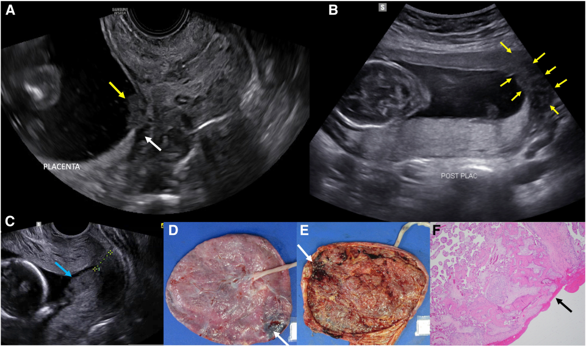

Diagnosis of Placental Abruption

Presumptive Diagnosis: Based primarily on presenting symptoms and history.

Ultrasound Utilization: Gold Standard

Placental Pathology: Examination of the placenta after delivery can provide further insights.